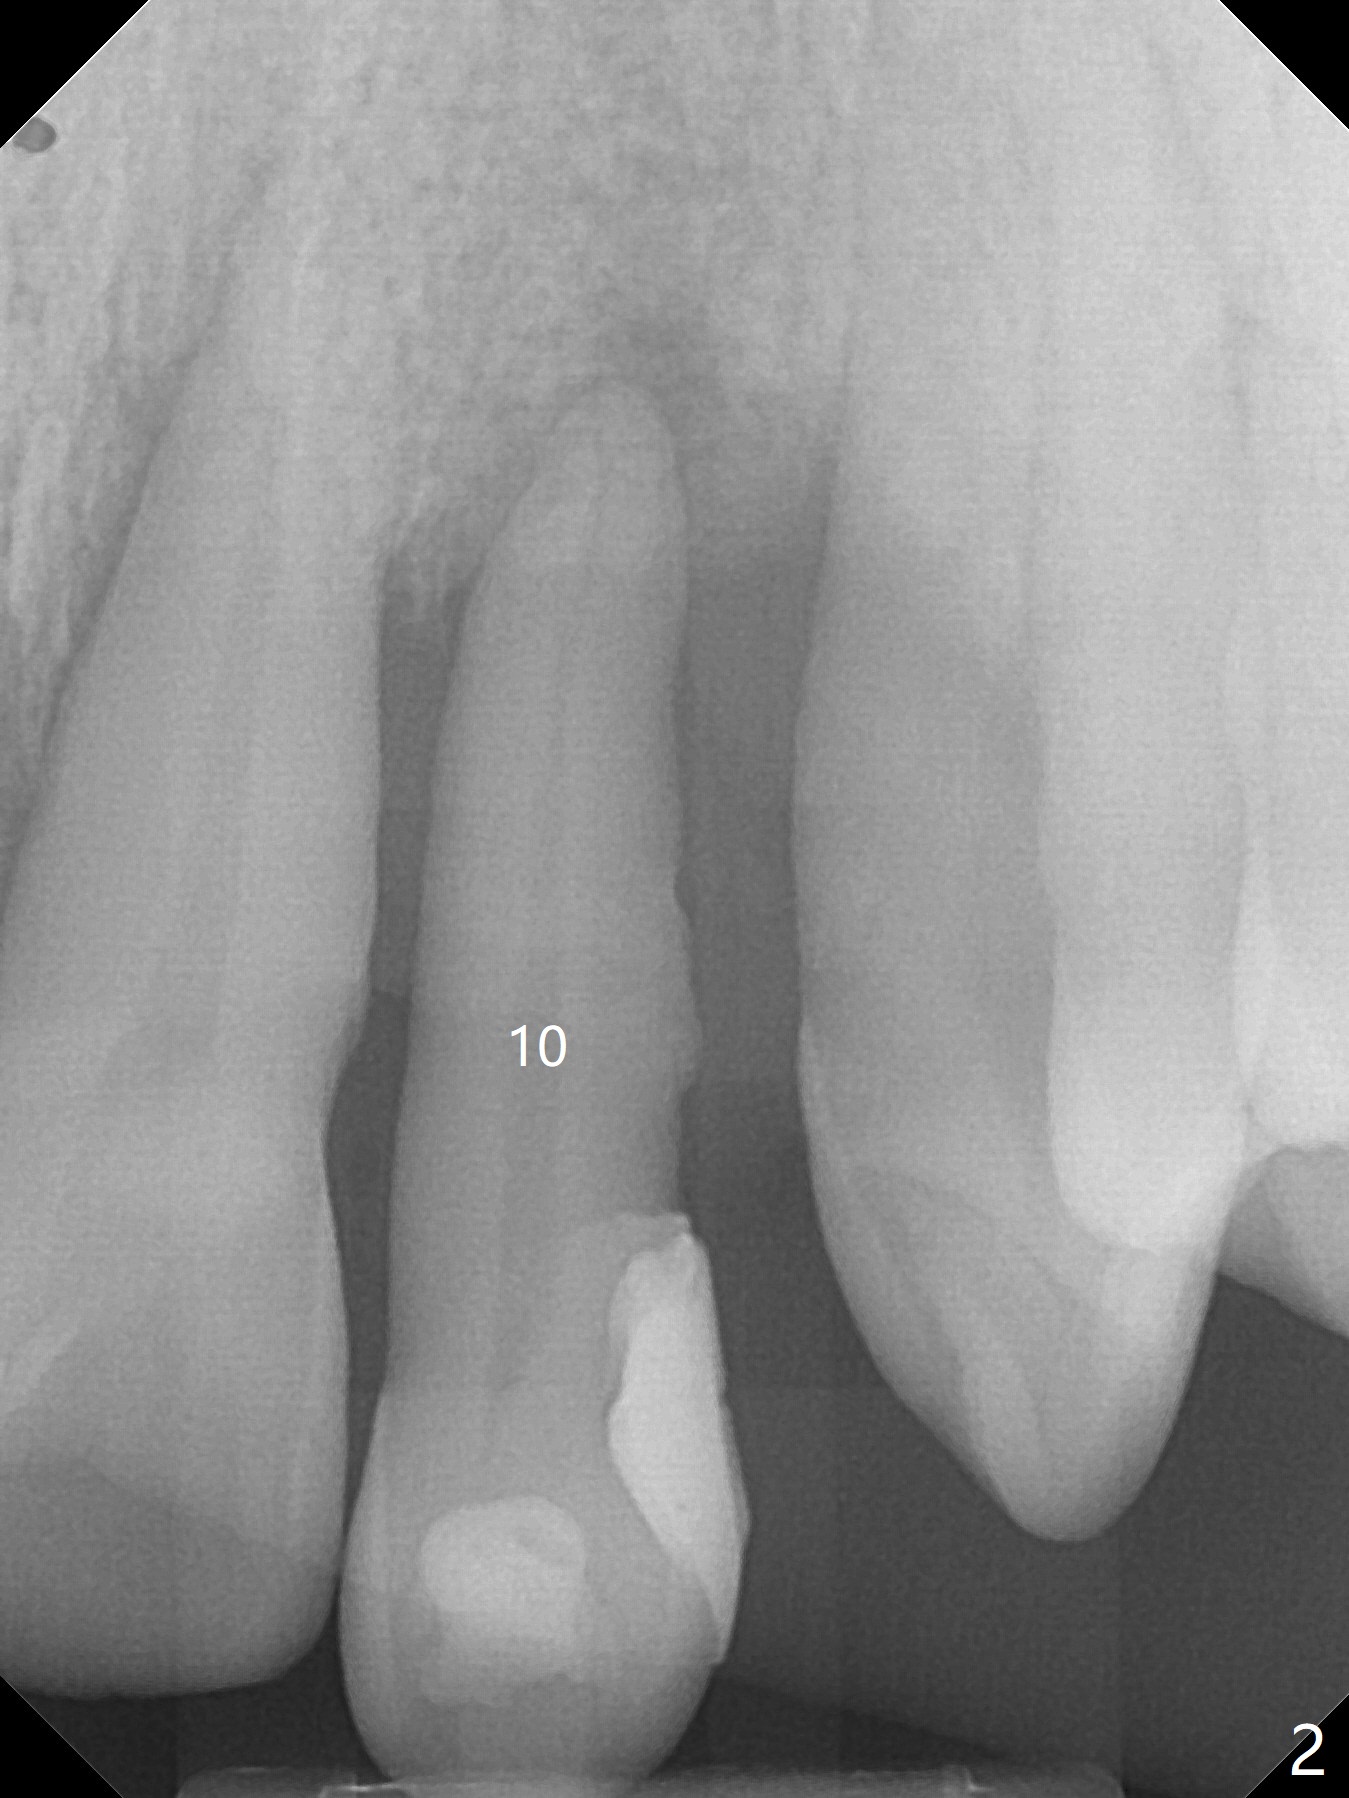

A 44-year-old man with generalized periodontitis (Fig.1) will return to clinic for #10 extraction (Fig.2) prior to brain tumor removal. Immediate implant (Fig.3) or not, sticky bone will be placed on the root surface of the neighboring teeth (Fig.4 red circles) after SRP. Place PRF membrane as early as possible, e.g, buccal, to avoid waste.